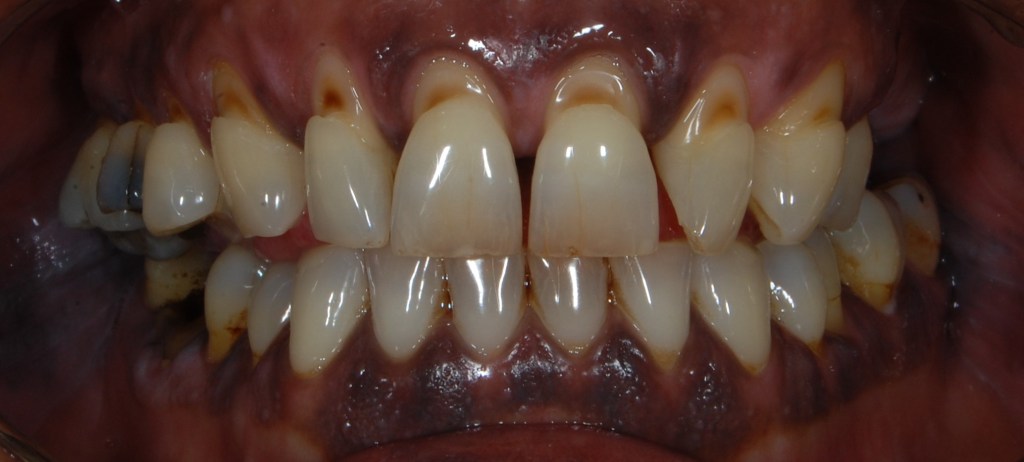

Kozmetikai kezelés: ínyvisszahúzódás és fognyaki kopások koronával történő korrekciója.

A választott korona típusa: CAD/CAM (komputer vezérelt tervezés/ megmunkálás) technológiával készült cirkónium (fémmentes) szóló koronák.

A választott fogszín: BL3 .

A protetikai munka elkészülésének ideje: 10 munkanap.